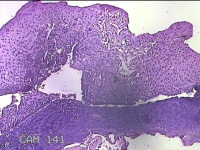

会厌肿物

性别

男

年龄

46岁

临床诊断

1.会厌肿物 2.慢性咽炎

一般病史

发复咽异物感3月余。

标本名称

大体所见

灰白粉红色肿物0.5x0.3x0.2cm一个,表面光滑。

良性病变。